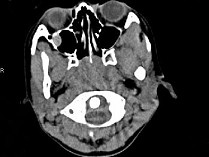

4.女,8岁,头痛,鼻塞半年余,CT如图所示,最可能诊断为 ( )![]() ![]() ![]() ![]() |

| 正确答案:C |